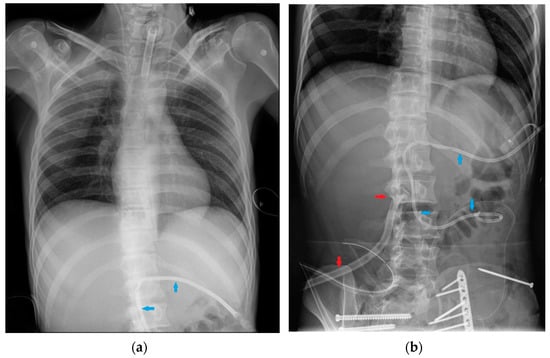

7. Chest Tubes

| Chest tubes | Kinking Extrapleural/intrafissural/intraparenchymal/misposition Mediastinum juxtaposition Diaphragmatic trespassing Mediastinal invasion (uncommon) |